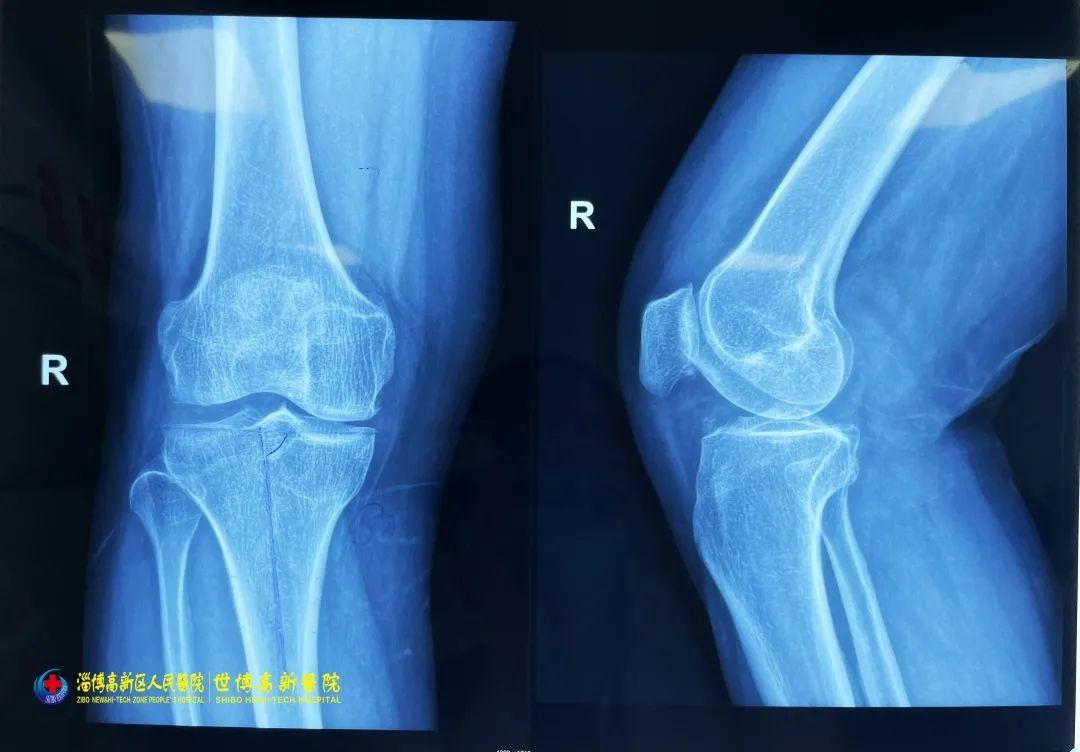

2022-12-01速豹新闻网淄博讯(记者 苗露 通讯员 于雪松)有人被砸伤了,快帮忙呼叫救援!21日下午,淄博高新区某建筑工地内一名工人不慎被重物砸伤